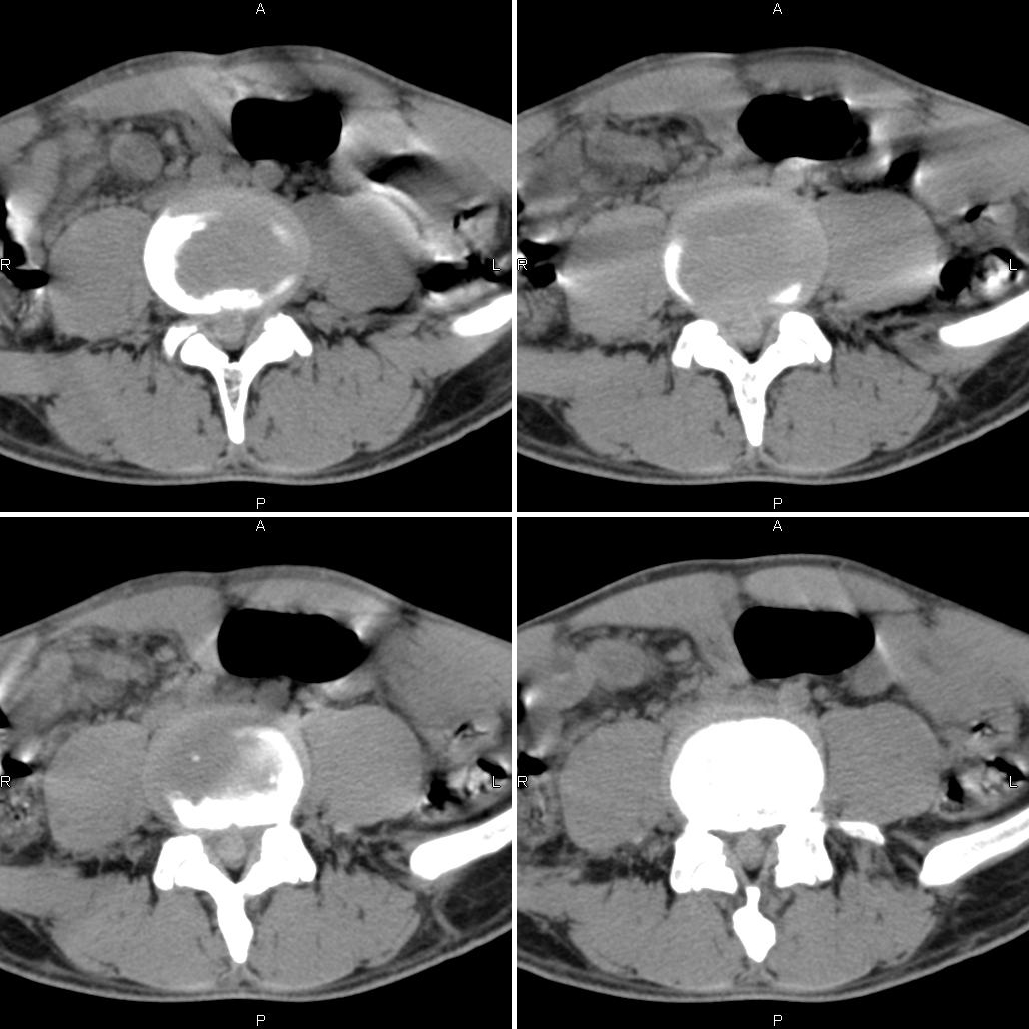

(结果公布:http://www.radida.com/bbs/forum.php?mod=viewthread&tid=70210) 男,40岁,左侧腰腿痛4~5天,外科检查:l3左侧压痛并下肢放射。

手术证实v0634:髓核孤立性脱出,易误诊为神经鞘瘤!

首先排除是否为机器原因造成,建议作空气校准后再扫描一次。如果排除机器原因,以髓核脱出可能性大。

考虑椎管内髓核游离